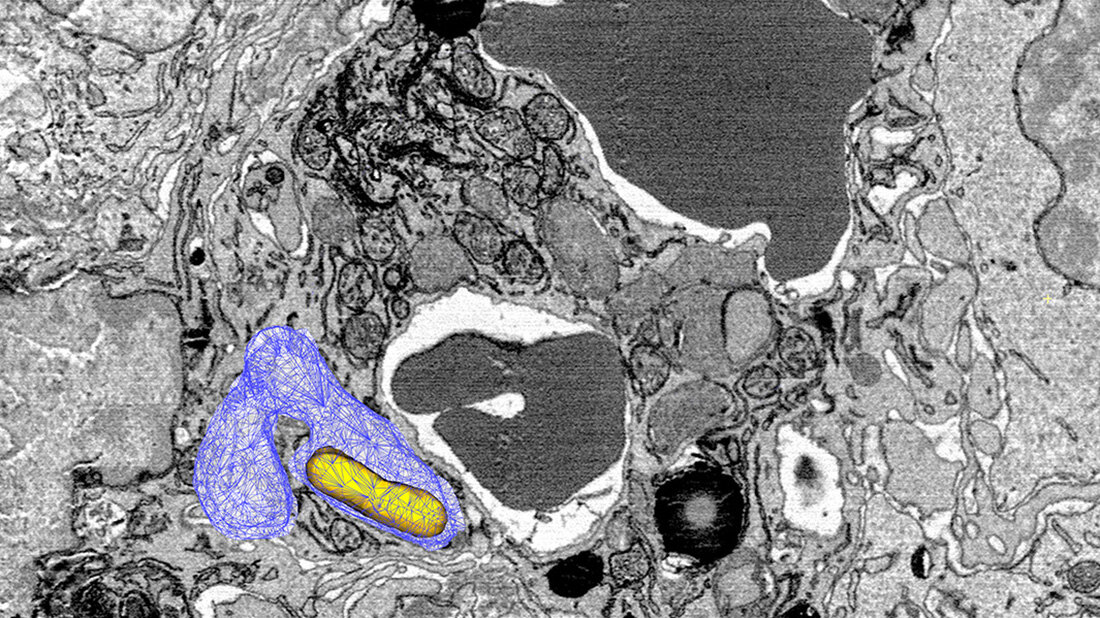

Die Bakterien verstecken sich in den Zellen, die besonders viel Eisen enthalten: den sogenannten Fresszellen. Hier können sie sich ungestört vermehren, obwohl sich die Makrophagen zunächst wehren und Eisen mithilfe eines Transportproteins entfernen. Doch Untersuchungen auf Einzelzellebene zeigten, wieso der Eisenmangel bei Salmonellen nicht wirkt. So sammeln sich die Salmonellen häufig in den Makrophagen der Milz, in denen alte oder beschädigte rote Blutkörperchen abgebaut werden. Hier liegt genügend Eisen vorhanden, dass sich die Salmonellen ungestört verbreiten können.

Dabei haben die Forschenden Unterschiede bei den Erregern entdeckt: „Wir haben in den Makrophagen der Milz zwei Populationen von Salmonellen entdeckt. Eine Gruppe lebt in eisenarmen Bereichen und vegetiert dort buchstäblich vor sich hin“, so Prof. Dr. Dirk Bumann. „Die zweite Population befindet sich in den Vesikeln, wo die roten Blutkörperchen abgebaut werden.“ Auch hier befördert das Transportprotein zwar das Eisen aus den Zellen hinaus, doch aufgrund des hohen Vorkommens reicht den Salmonellen das restliche Eisen zur Verbreitung aus. Sie sorgen dafür, dass die Erkrankung bestehen bleibt.